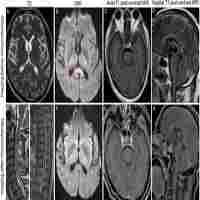

| Abstract | Background Reversible splenial lesion syndrome (RESLES) was reported to be associated with variable entities. However, much less is known about the cases in which the mental disorders act as the only manifestation. Method Total ten patients of RESLES were obtained in this retrospective study from Shenzhen Kangning Hospital. T1-fluid attenuated inversion recovery (T1-FLAIR), T2-weighted images, T2-FLAIR, diffusion-weighted images and apparent diffusion coefficient map were performed on all the patients. Clinical manifestations, laboratory examination results, magnetic resonance imaging (MRI) findings, treatments and outcomes were analyzed. Result All patients showed different mental disorders as the only manifestation. There were two cases of alcohol abuse, one of Asperger’s syndrome with malnutrition, one of infection and one of invasive pituitary adenoma. The other cases were diagnosis as major depressive disorder, dissociative and conversion disorders, undifferentiated somatoform disorder, unspecified psychosis and bipolar disorder, respectively. Three patients were completely recovered while the clinical symptoms of rest seven patients partially recovered at the follow-up three months later. Oval-shaped lesion centered on the splenial of corpus callosum (SCC) was observed in all patients using MRI. The lesions of SCC of all patients were completely resolved within five weeks. Conclusions We found that RESLES might only showed mental symptoms. On the one hand, for the patients with acute mental disorders, clinicians should be alert to the possibility of RESLES caused by physical disease. On the other hand, we suggest that mental disorder might be a precipitating factor of RESLES. |